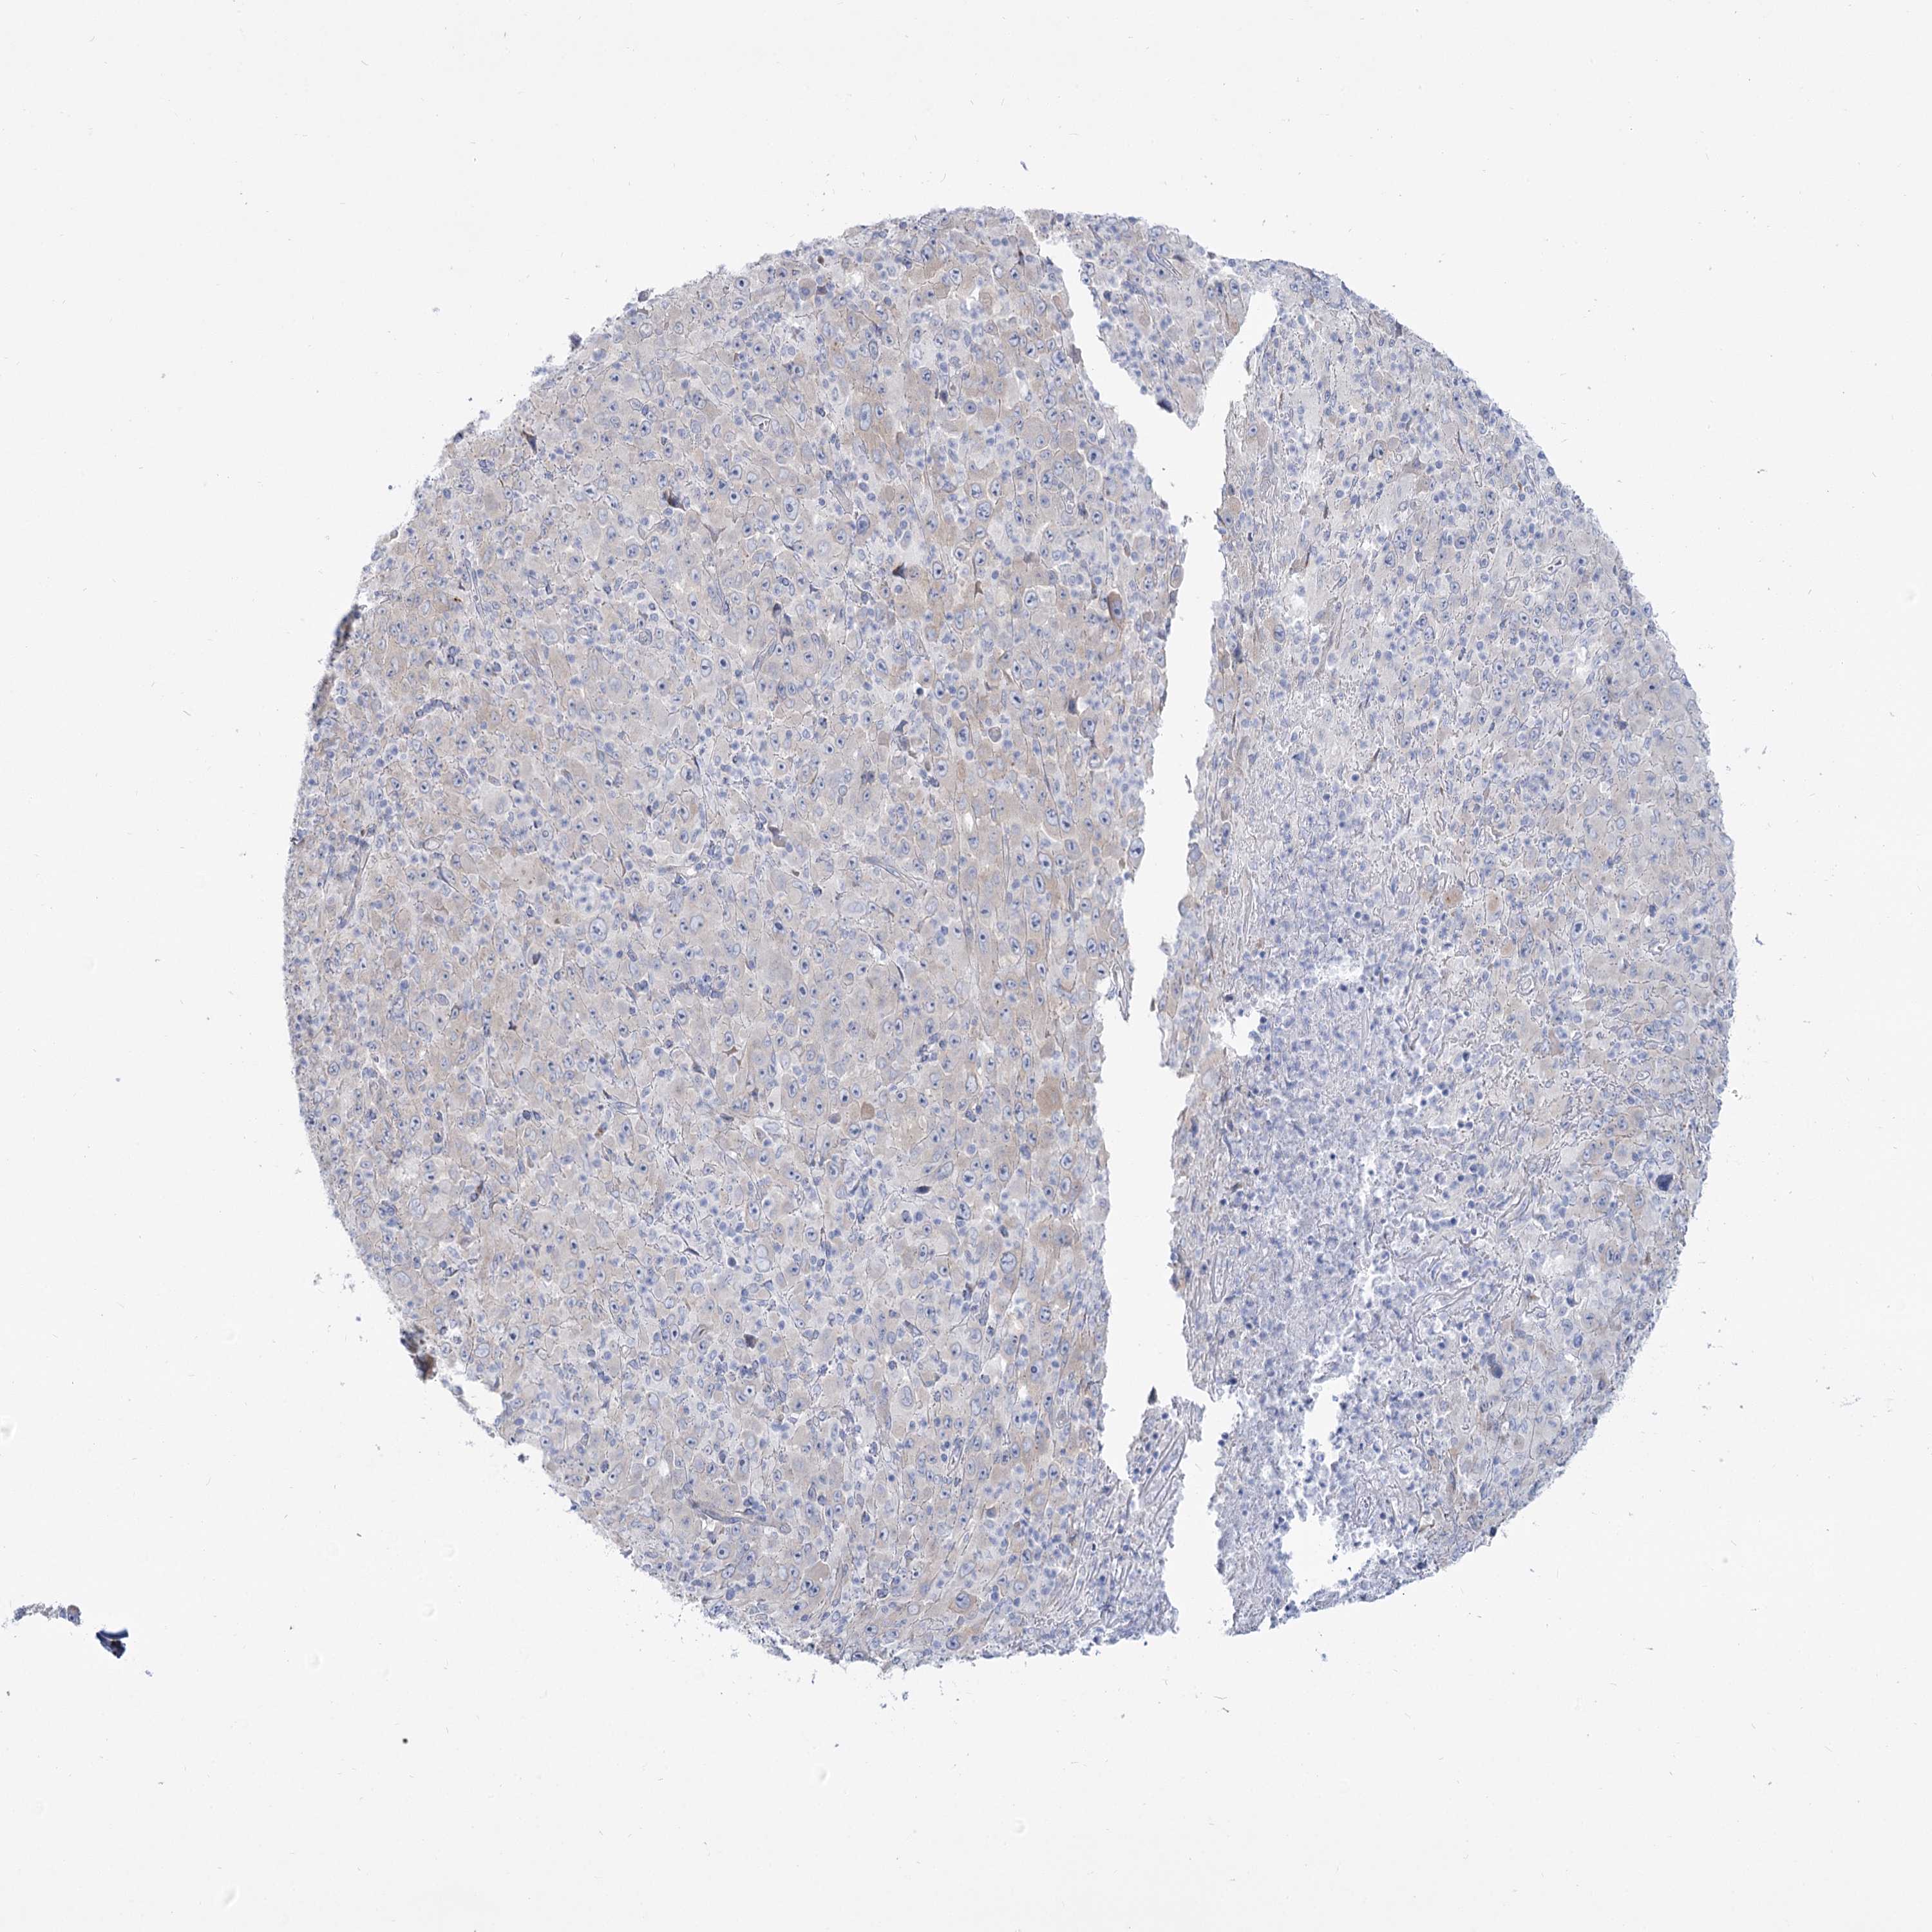

MELANOMA - Protein expressioni

A mouse-over function shows sample information and annotation data. Click on an image to view it in a full screen mode. Samples can be filtered based on level of antibody staining by selecting one or several of the following categories: high, medium, low and not detected. The assay and annotation is described here.

Note that samples used for immunohistochemistry by the Human Protein Atlas do not correspond to samples in the TCGA dataset.

Antibody stainingi

Antibody staining in the annotated cell types in the current human tissue is reported as not detected, low, medium, or high, based on conventional immunohistochemistry profiling in selected tissues. This score is based on the combination of the staining intensity and fraction of stained cells.

Each image is clickable and will lead to virtual microscopy that enables deeper exploration of all samples and also displays staining intensity scores, fraction scores and subcellular localization as well as patient and tissue information for each sample.

Antibody HPA038208

Antibody HPA038209

Malignant melanoma, NOS

Malignant melanoma, Metastatic site